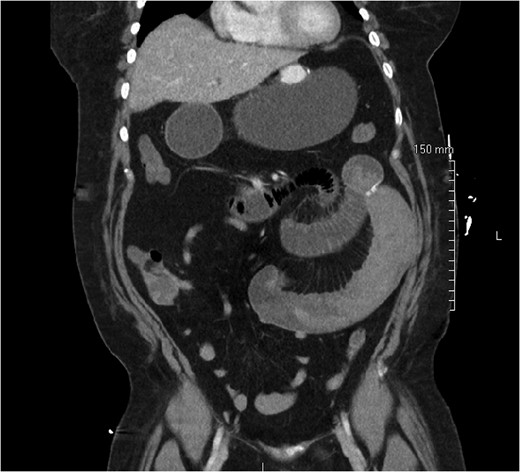

On post-operative day 1, she complained of nausea, vomiting and abdominal pain, though symptoms were consistent with an expected post-operative course. On post-operative day 2, however, she developed a leukocytosis of 15 600/mm3 and an intermittent tachycardia ranging from 85 to 118 bpm. An abdominal CT was obtained, which demonstrated a SBO with a transition point distal to the jejunojejunostomy anastomosis (Fig. 1). The patient was taken to the operating room for diagnostic laparoscopy. Upon initial inspection, there was no evidence of a mechanical cause for obstruction such as kinking or adhesions. However, the bowel proximal to the common channel appeared dilated and discolored (Fig. 2). Esophagogastroduodenoscopy (EGD) was performed to inspect the luminal mucosa, which was pink and well-perfused. Inspection distal to the jejunojejunostomy revealed a 50 cm section of bowel that was firm and appeared to be the point of obstruction. An enterotomy was made in the proximal common channel, which revealed a large intraluminal clot (Fig. 3). This was removed piecewise with a combination of suction and manual extraction (Fig. 4). There was no evidence of active bleeding or leakage from the jejunojejunostomy anastomosis. Due to the friability of the intestinal walls and absence of active bleeding, the anastomosis was not revised and the enterotomy was primarily closed.

Improvement in small bowel appearance after evacuation of clot with suction and manual extraction.